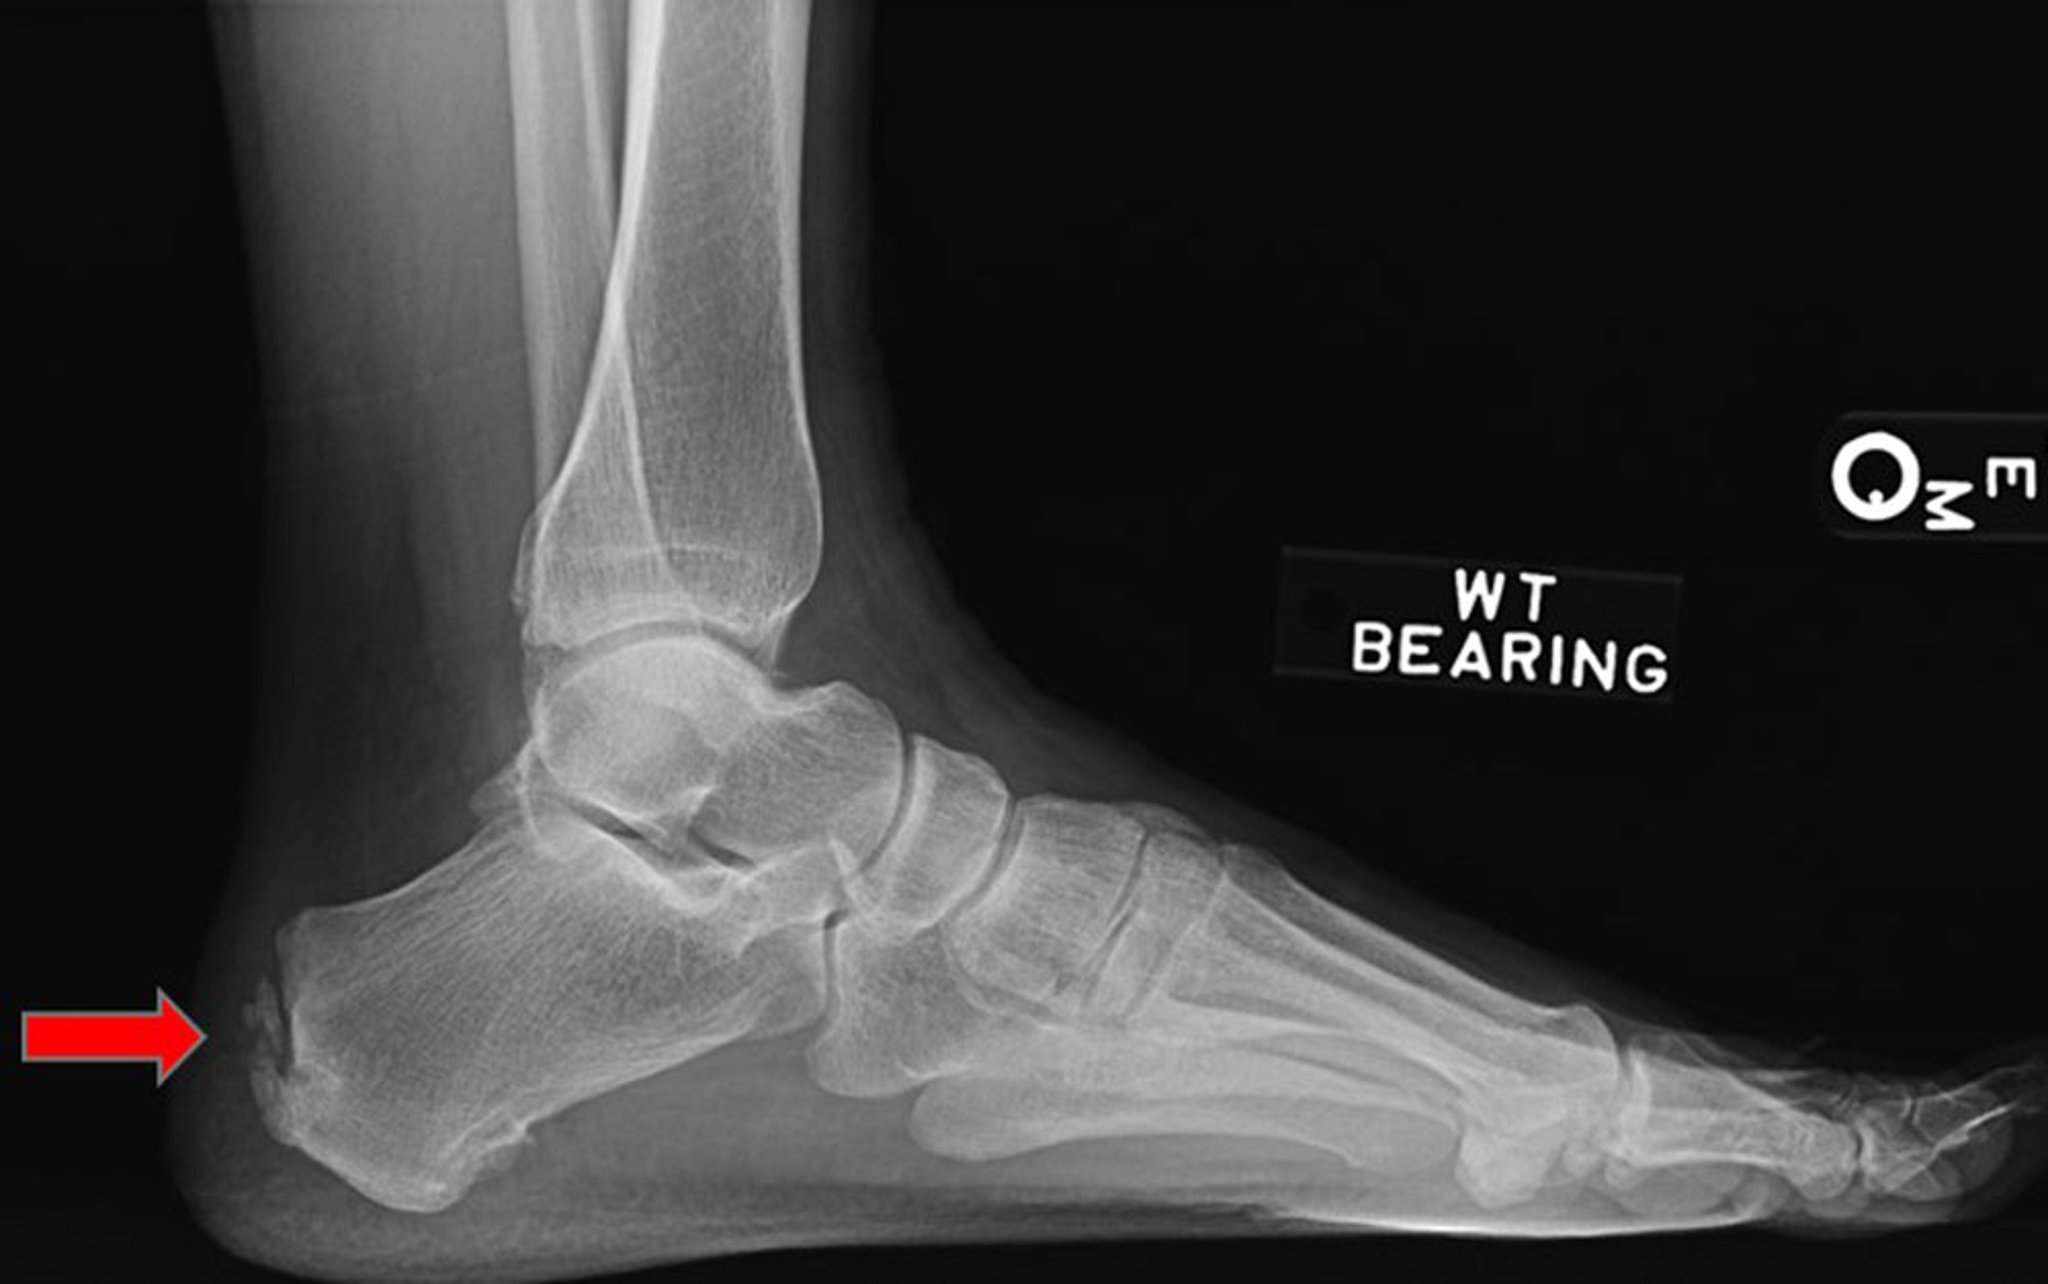

Achilles Tendon Enthesopathy

This lateral radiograph shows Achilles tendon enthesopathy (arrow).

Image courtesy of James C. Connors, DPM.